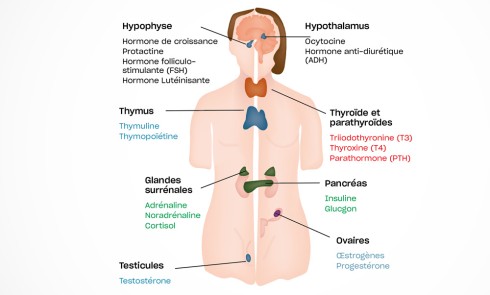

Sur le plan parodontal, il existe une gingivite résiduelle à une gingivectomie (la patiente étant sous anti-épileptiques).